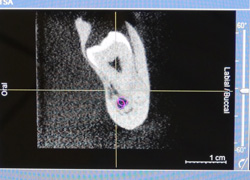

Allerdings bieten wir hier auch die Option einer kompletten digitalen 3D Planung an.